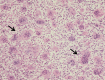

Giant cell tumor (GCT) of bone is a locally aggressive benign neoplasm that is associated with a large biological spectrum ranging from latent benign to highly recurrent and occasionally metastatic malignant bone tumor. It accounts for 4-10% of all bone tumors and typically affects the meta-epiphyseal region of long bones of young adults. The most common site involved is the distal femur, followed by the distal radius, sacrum, and proximal humerus. Clinical symptoms are nonspecific and may include local pain, swelling, and limited range of motion of the adjacent joint. Radiographs and contrast-enhanced magnetic resonance imaging (MRI) are the imaging modalities of choice for diagnosis. Surgical treatment with curettage is the optimal treatment for local tumor control. A favorable clinical outcome is expected when the tumor is excised to tumor-free margins, however, for periarticular lesions this is usually accompanied with a suboptimal functional outcome. Local adjuvants have been used for improved curettage, in addition to systematic agents such as denosumab, bisphosphonates, or interferon alpha. This article aims to discuss the clinicopathological features, diagnosis, and treatments for GCT of bone.